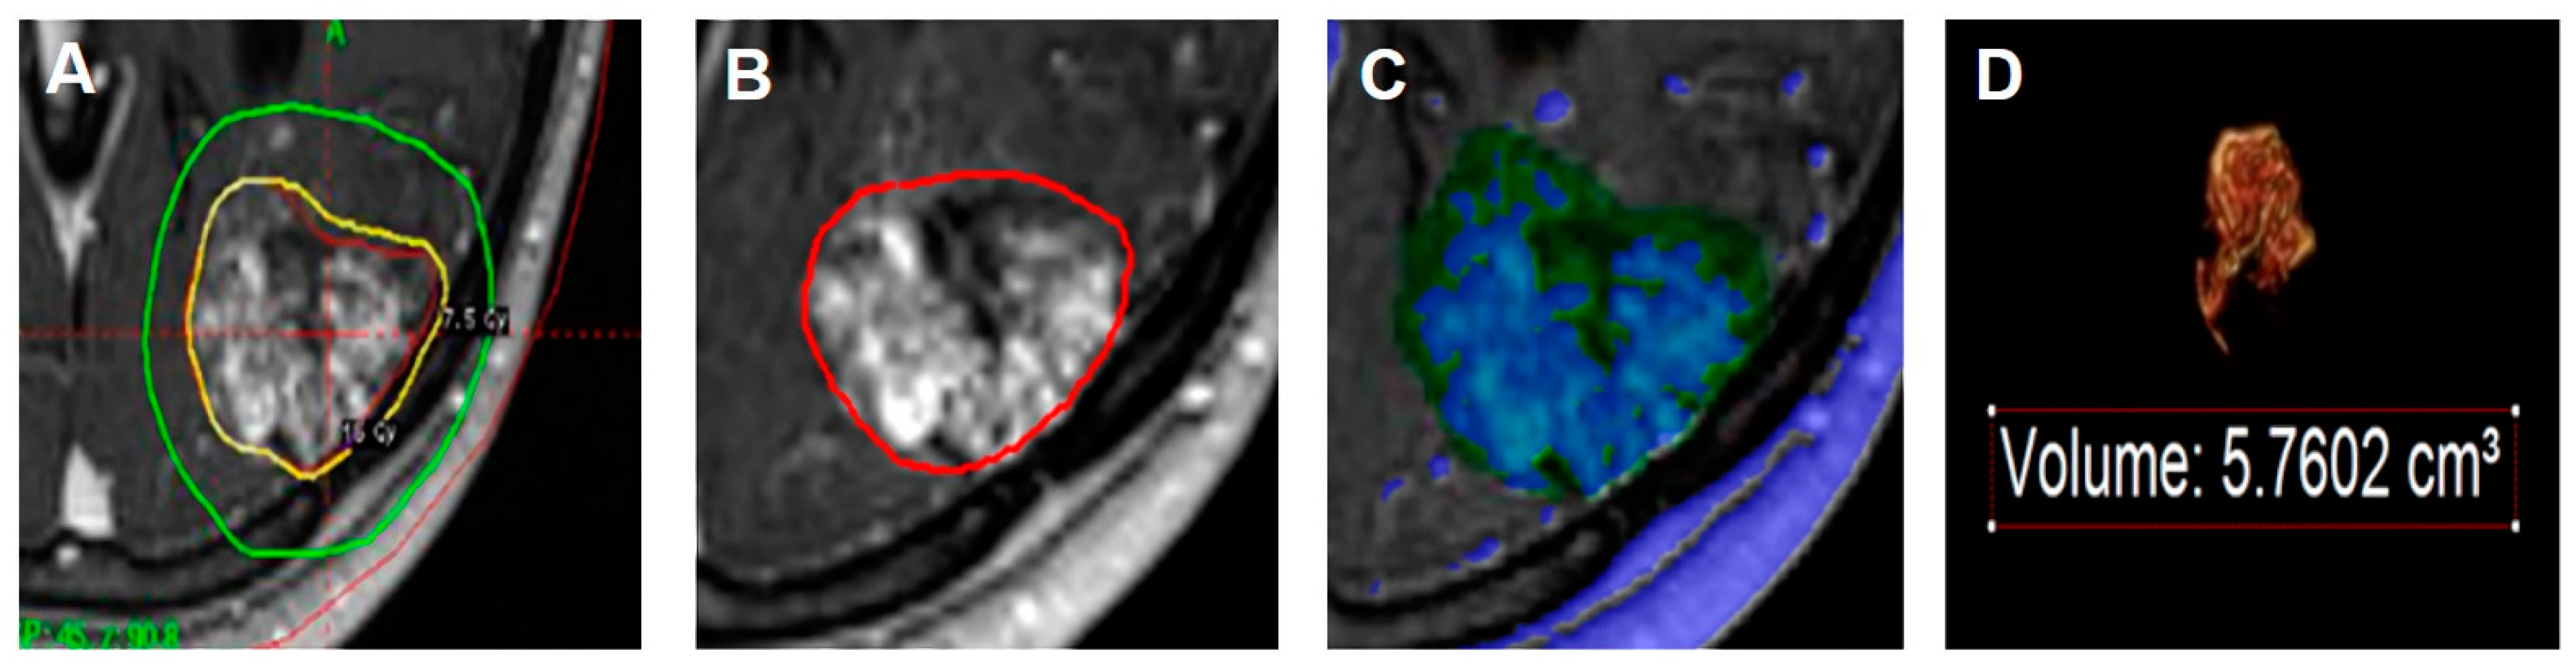

- Peng, S.J.; Lee, C.C.; Wu, H.M.; Lin, C.J.; Shiau, C.Y.; Guo, W.Y.; Pan, D.H.; Liu, K.D.; Chung, W.Y.; Yang, H.C. Fully automated tissue segmentation of the prescription isodose region delineated through the Gamma knife plan for cerebral arteriovenous malformation (AVM) using fuzzy C-means (FCM) clustering. Neuroimage Clin. 2019, 21, 101608. [Google Scholar] [CrossRef] [PubMed]

- Lee, C.C.; Yang, H.C.; Lin, C.J.; Chen, C.J.; Wu, H.M.; Shiau, C.Y.; Guo, W.Y.; Hung-Chi Pan, D.; Liu, K.D.; Chung, W.Y.; et al. Intervening Nidal Brain Parenchyma and Risk of Radiation-Induced Changes After Radiosurgery for Brain Arteriovenous Malformation: A Study Using an Unsupervised Machine Learning Algorithm. World Neurosurg. 2019, 125, e132–e138. [Google Scholar] [CrossRef] [PubMed]